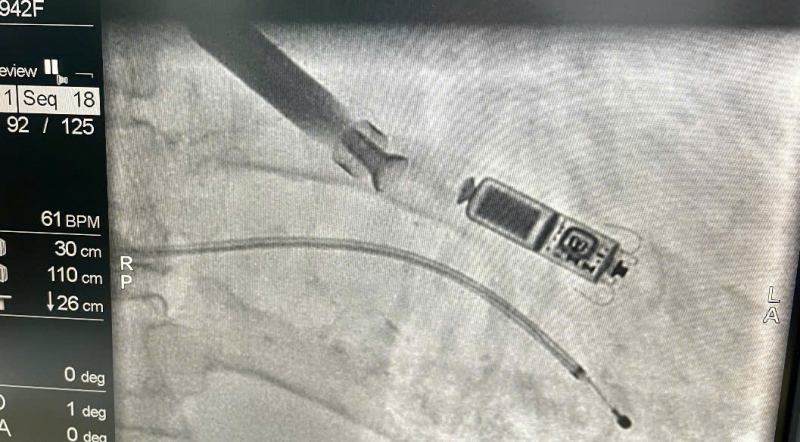

O procedimento foi realizado pelo Dr. Nguyen Quoc Khoa e pela equipe de implante de marca-passo do Hospital 30-4, sob o apoio direto do Dr. Vo Thanh Nhan, Diretor do Centro de Cardiologia Intervencionista do Hospital Tam Anh, na Cidade de Ho Chi Minh. A equipe implantou o dispositivo através da veia femoral utilizando um cateter, posicionando-o com alta precisão na câmara cardíaca. A intervenção transcorreu sem intercorrências e o dispositivo funcionou de forma estável imediatamente após o procedimento.